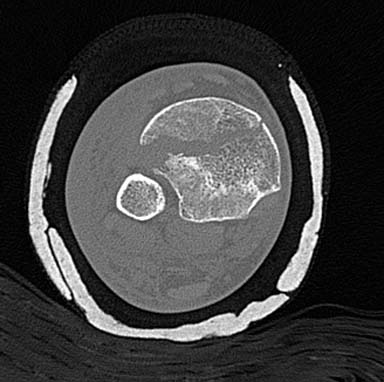

Первый случай, где перелом в результате падения с небольшой высоты, где мортиз рентген снимок показал отстутствие укорочения наружной

лодыжки и КТ срезы подсказали направления атаки. После такой фиксации нет надобности в гипсовой повязке, брейс и через две недели движения в

суставе без нагрузки.